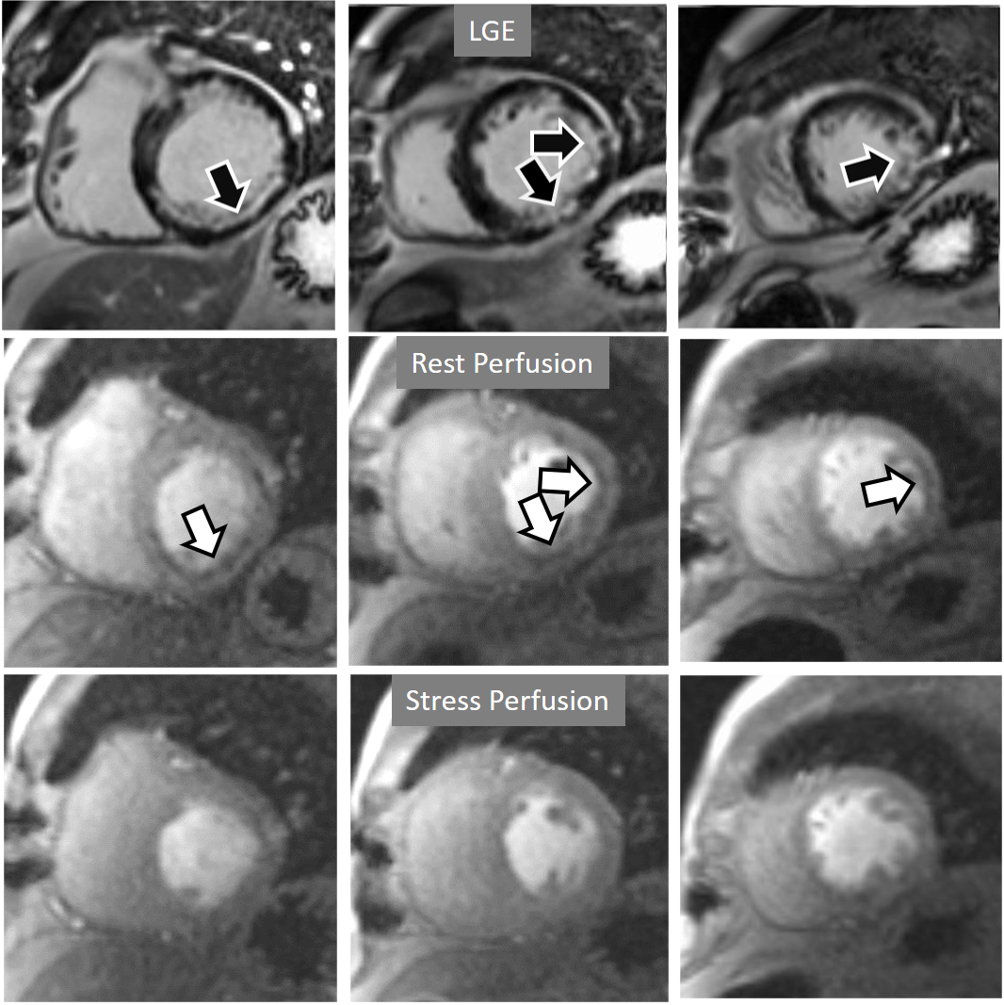

Perfusion defects in different territories can be detected in case of multivessel disease (Fig. 7) and, in patients with severe 3-vessel CAD, the perfusion study may show a global, intense, persistent defect which is readily recognizable (Fig. 8).

Fig. 7.Two-vessel perfusion defect. Stress perfusion defects at the anterior (white arrows) and inferior (black arrows) walls, not present at rest. Angiography (right panels) shows significant stenoses (white arrows) of the LAD (upper panel) and the right coronary artery (RCA) (lower panel).